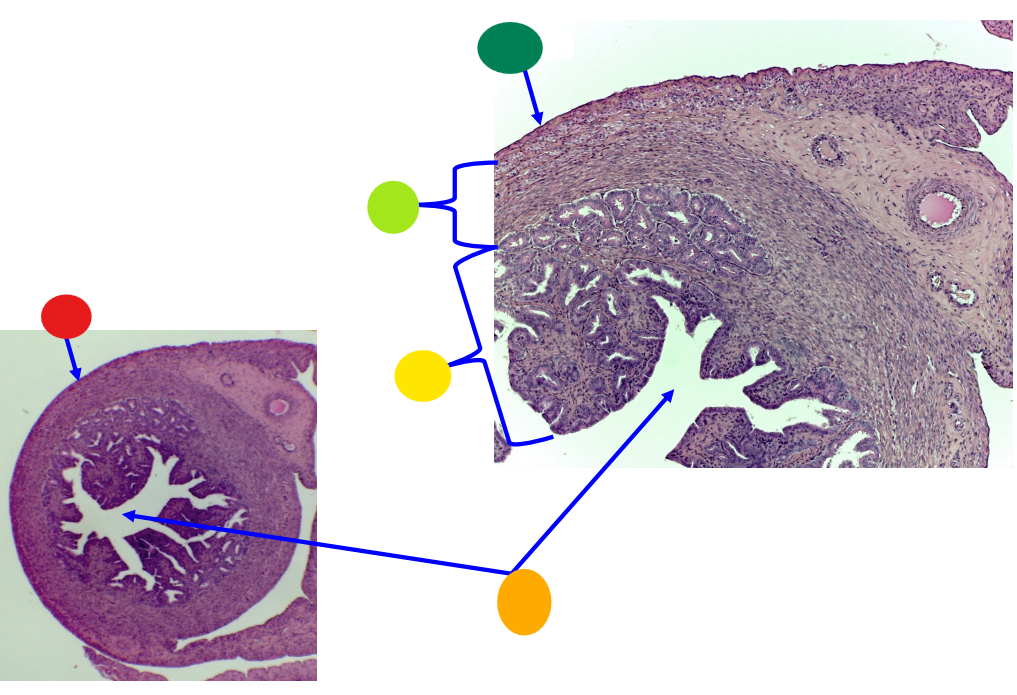

red

tunica albuginea

orange

primordial follicles

yellow

follicular cells

light green

primary oocyte

dark green

granulosa cells

light blue

primary follicles

what is this?

ovary

red

primordial follicles

red

primary follicles

red

tunica albuginea

orange

primary oocyte

yellow

primordial follicles

red

tunica albuginea

orange

primordial follicles

red

primary follicle

orange

secondary follicles

what is this

tertiary follicle